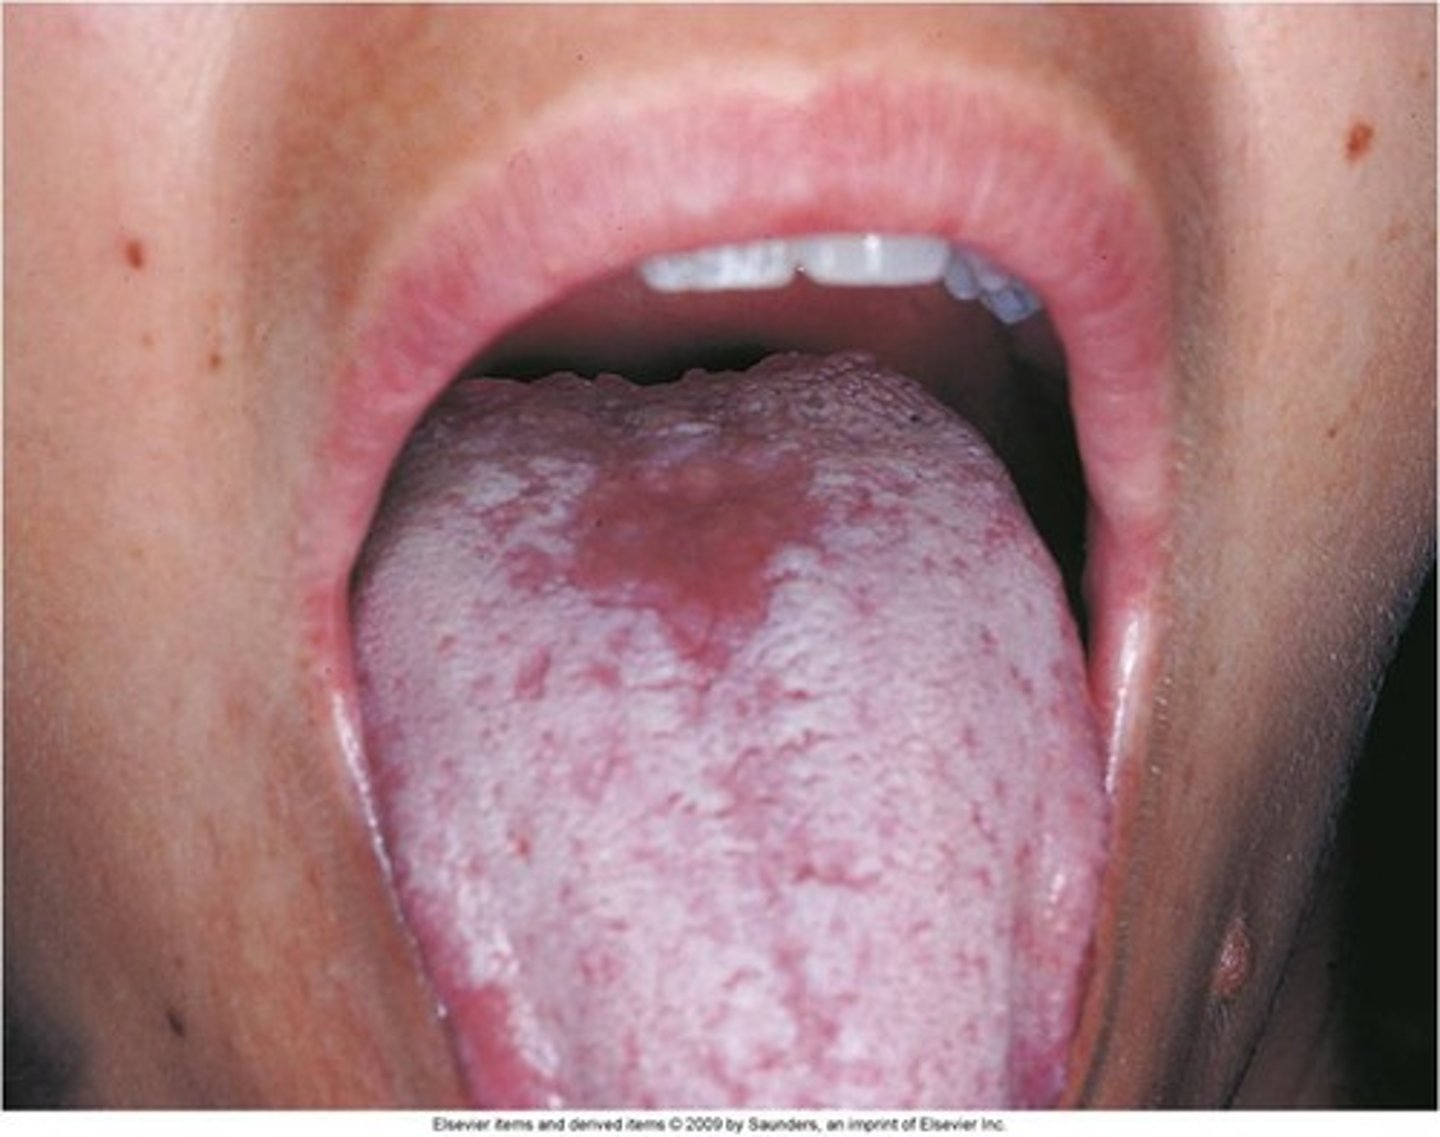

Median Rhomboid Glossitis (Central Papillary Atrophy) is type of ___ infection.

Tx

candida

nystatin

Oral hairy leukoplakia (AIDS)

presents as white plaque usually on the lateral border of the tongue that does not rub off. Associated with __ and ___

Presents as a white mucosal plaque that does not rub off, usually on the lateral border of the tongue; associated with EBV and AIDS